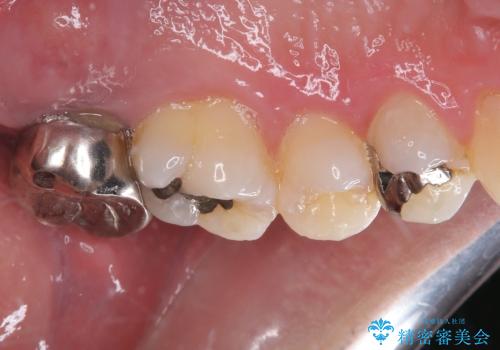

- 奥歯の周りの歯肉が腫れており、噛む度に痛みを感じるとのことで来院された患者様です。

レントゲンや診察を行ったところ、抜歯となる可能性はありましたが、まずは銀歯を外した上で根管治療を行うことが可能であるか判断することが先決であるとご説明し、根管治療とインプラント治療の双方をご案内し、治療を開始することとしました。

骨の透過像が非常に大きく、根管も大きく削られていたため、歯根破折による抜歯の可能性がありましたが、根管治療可能な状態でした。